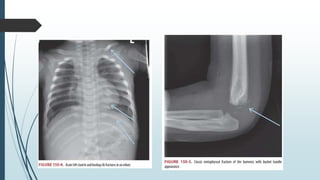

Skeleton • incompletely calcified ,

contains multiple active

growth centers, weaker

epiphysis and is more pliable

• internal organ damage is often

damage noted without bony

fractures

• pulmonary contusion is common

but rib fractures is not

The presence of skull and/or rib

fractures in a child

- suggests the transfer of a massive

amount of energy

- in this case, underlying organ

injuries, such as traumatic brain

injury and pulmonary

• High index of intrathoracic

injury without rib fractures